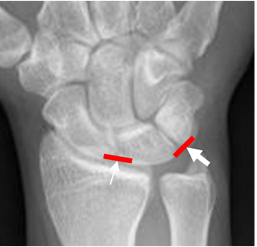

Fig 1. Ligamentos intrínsecos.

Rx AP. Ligamento escafolunado (Flecha delgada) y semilunopiramidal (Flecha gruesa).